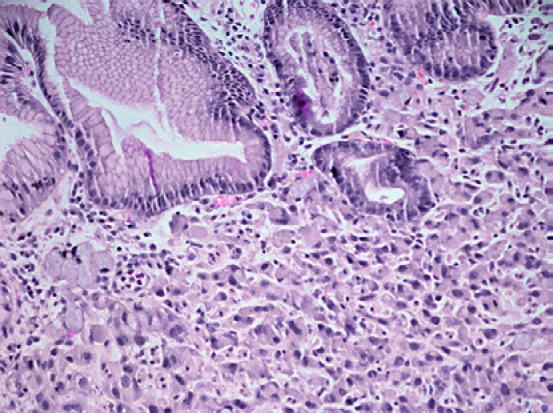

Neuroendocrine carcinoma (NEC) consisting of poorly differentiated tumor cells with many mitosis forming solid sheets and nests